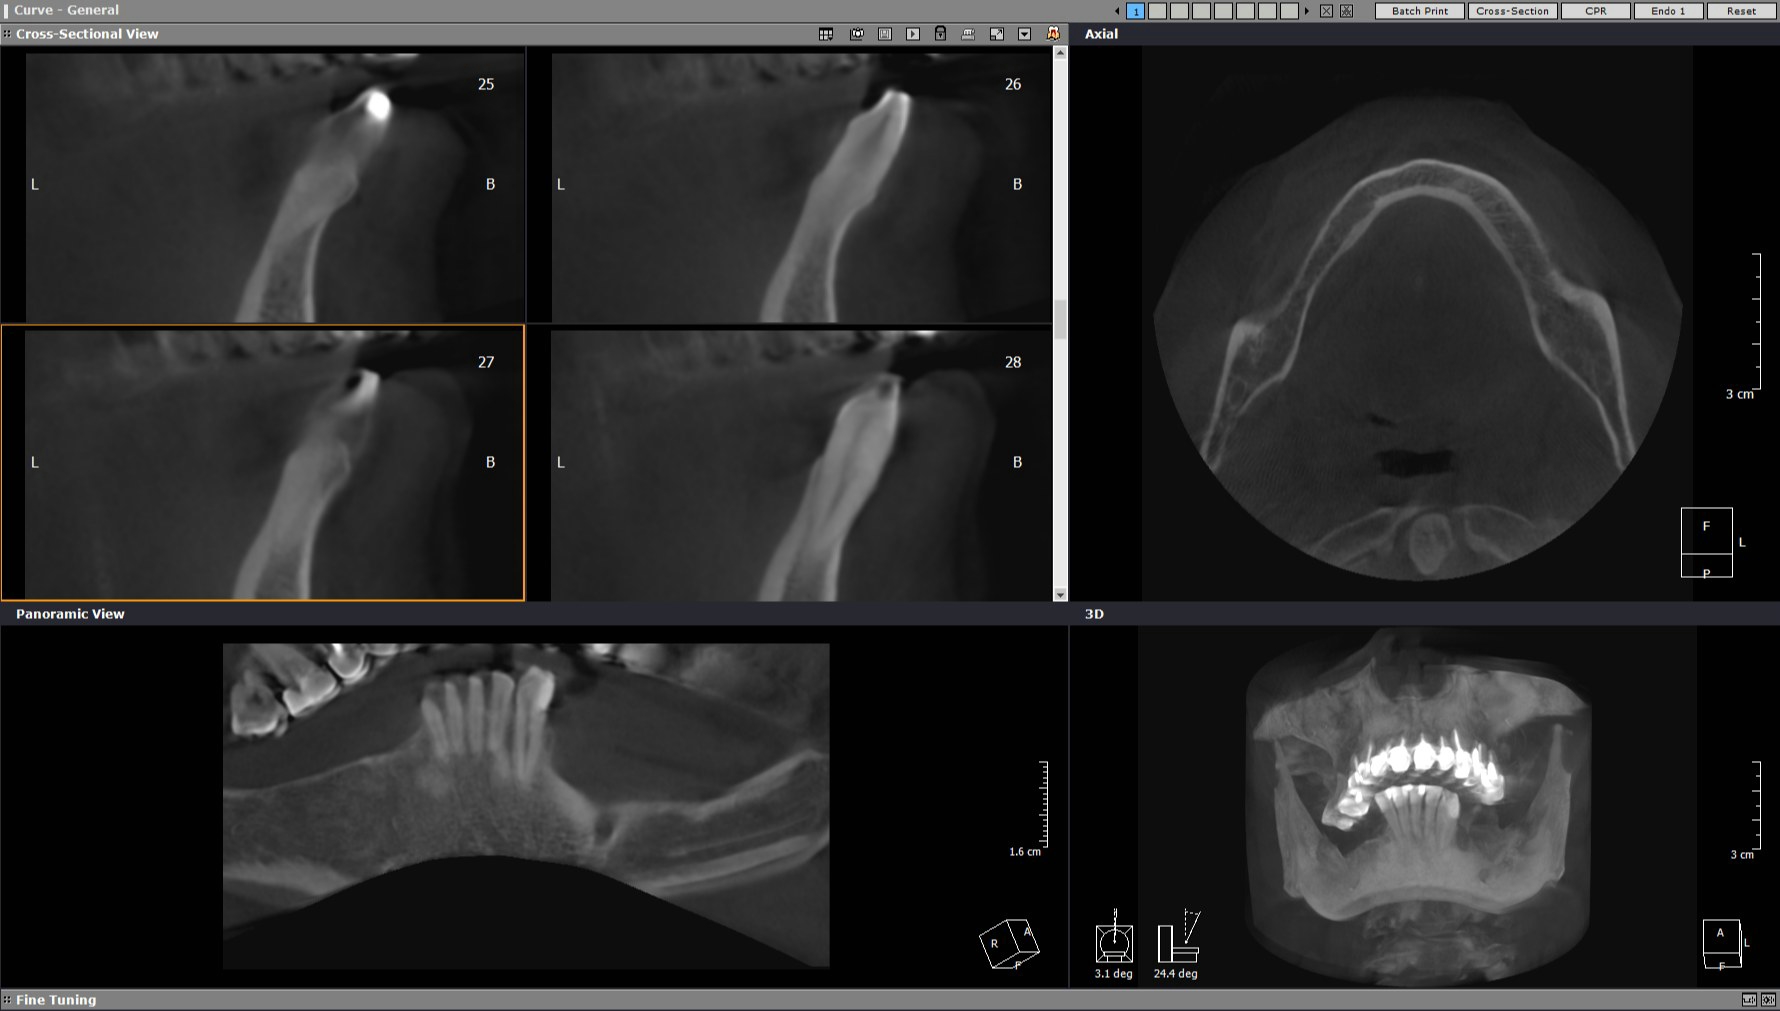

| КТ до имплантов |